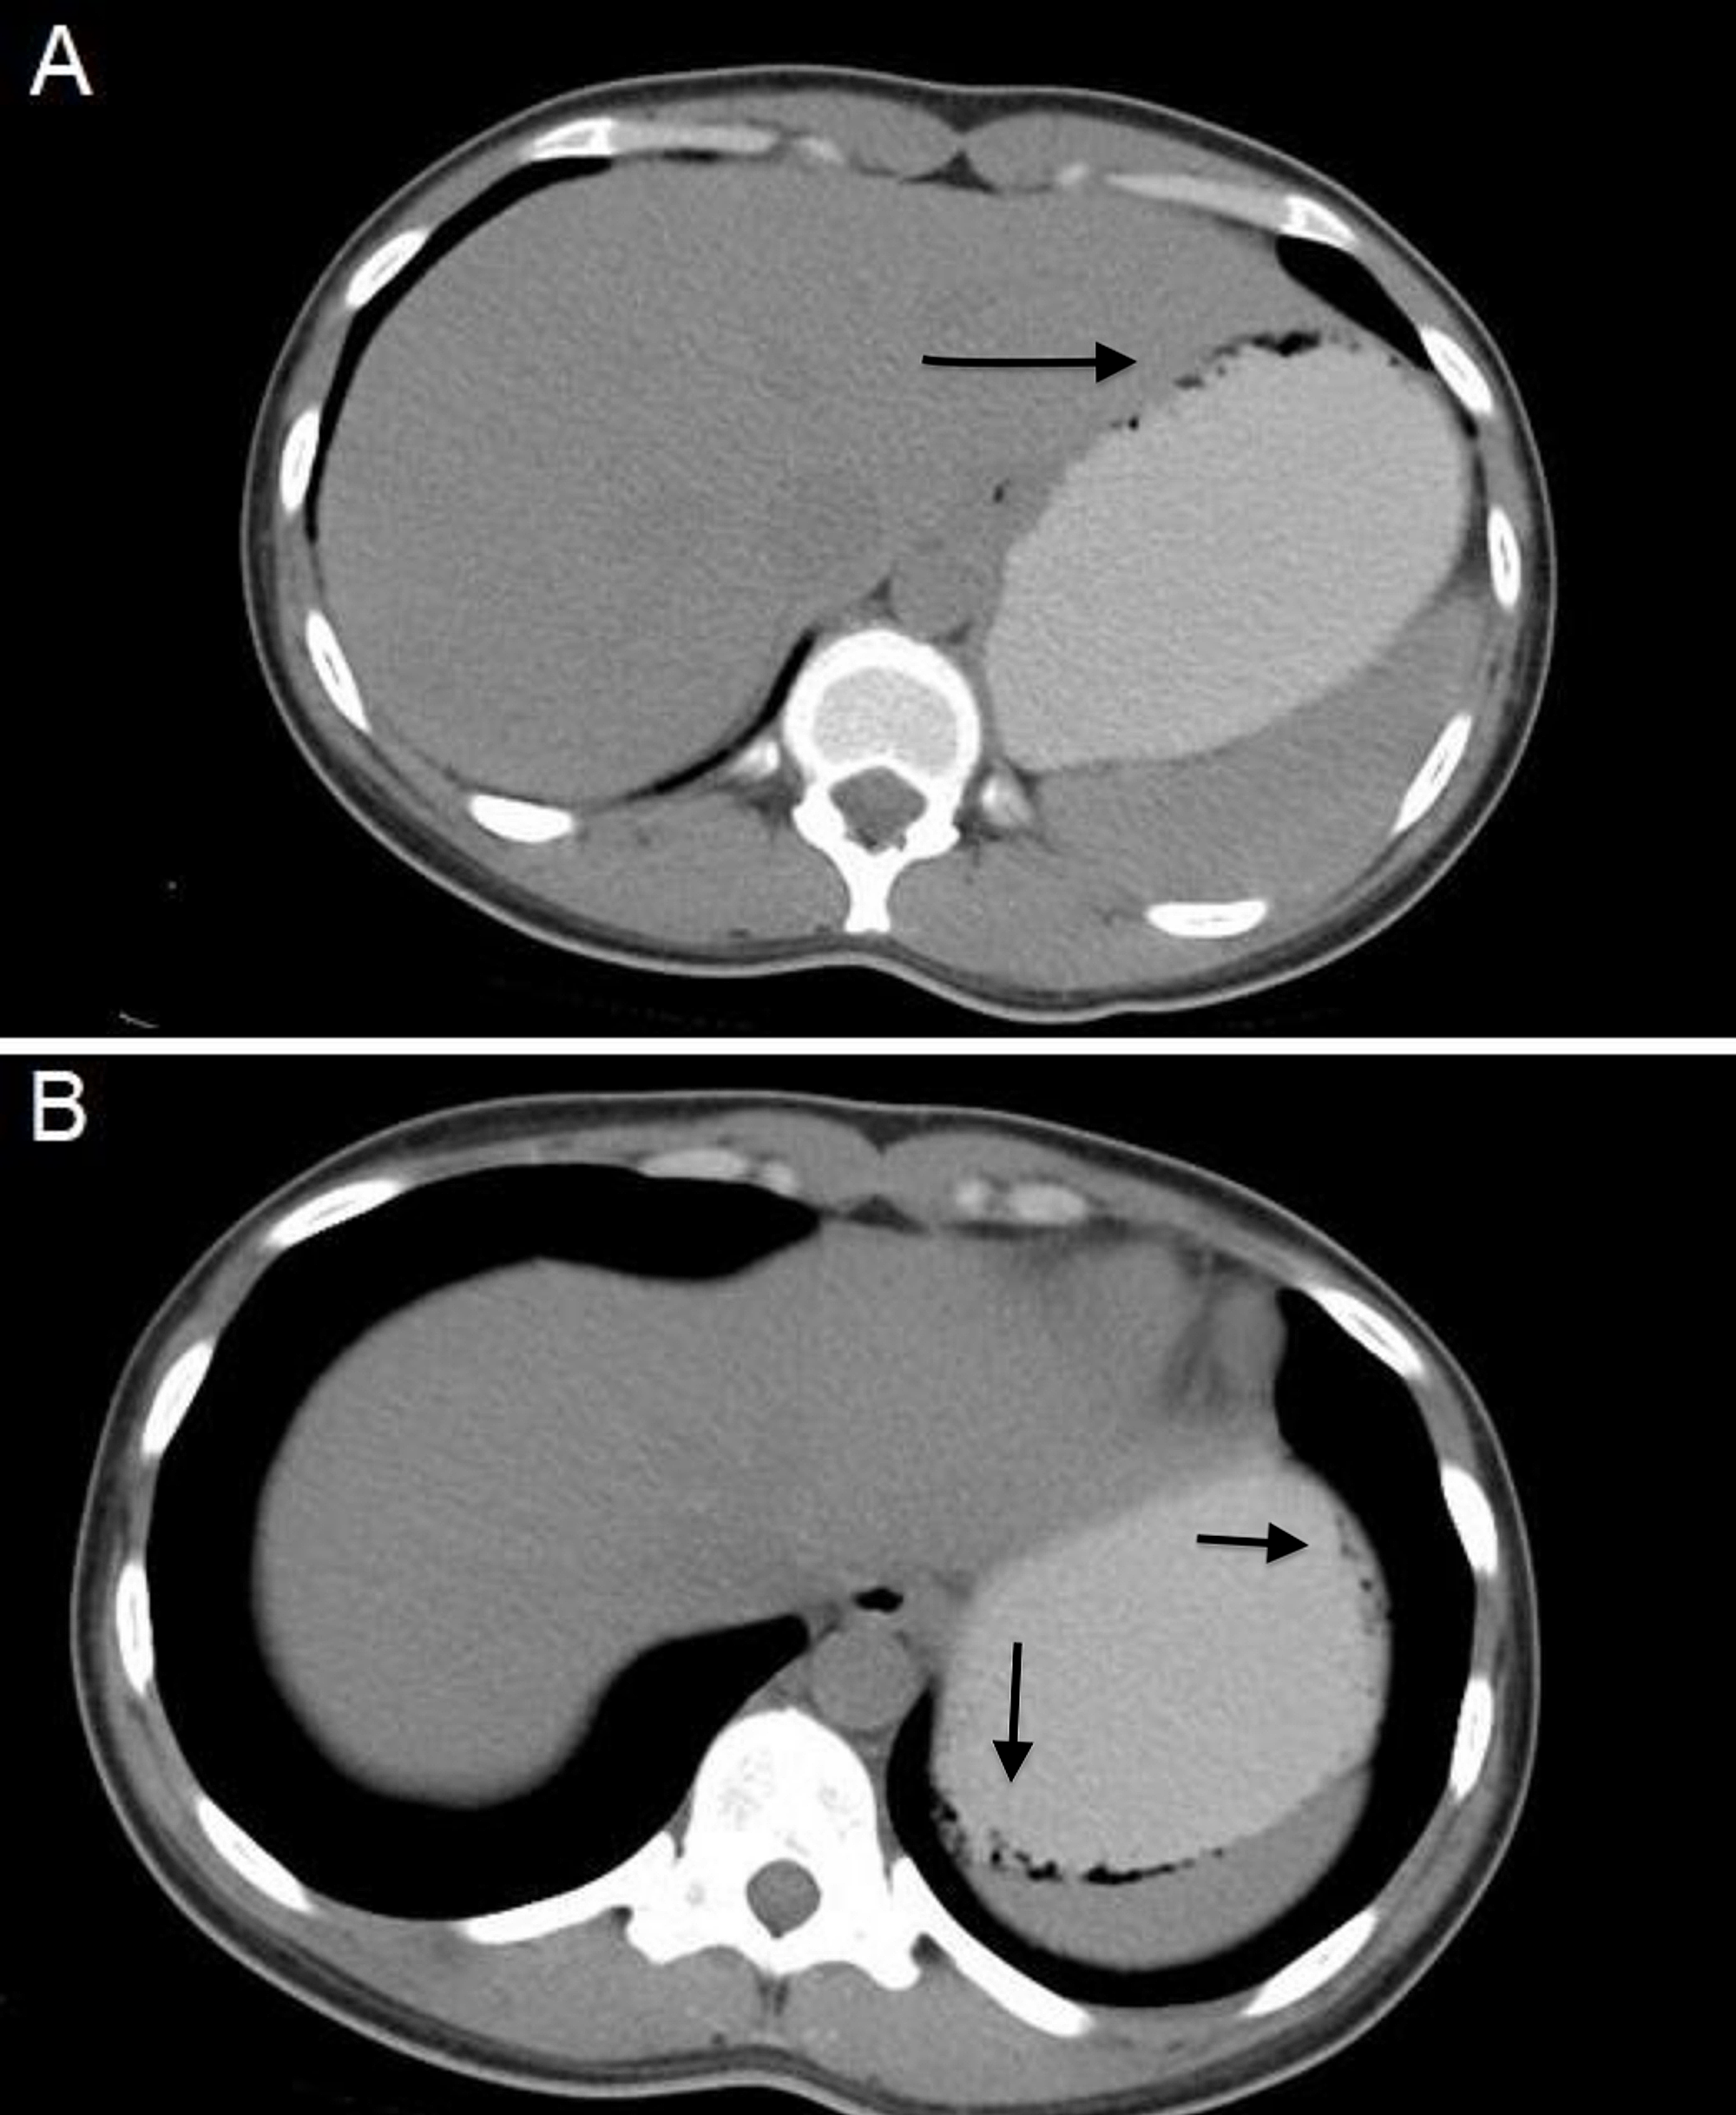

Gastric pneumatosis GP has been classified as either idiopathic 15 of cases or secondary 85 of cases ranging clinically from a benign condition to a fulminant disease 13-15The clinician challenge in front of this entity is defining weather we are in front of gastric emphysema GE or emphysematous gastritis EG 16-18 as the two entities give contrasting prognosis.

Emphysematous gastritis is a rare medical condition characterized by the presence of intra-mural air in the stomach associated with portal venous air tracking to a variable degree. Review of Image-Defined Risk Factors in Neuroblastoma. Basics of Imaging and Treatment. Emphysematous gastritis is a rare medical condition characterized by the presence of intra-mural air in the stomach associated with portal venous air tracking to a variable degree. Emphysematous gastritis is a rare disease with gastric inflammation and intramural gas formation due to gas-forming microorganisms.

Infection with presence of intramural gas and systemic toxicity is a rare condition and its mortality rate reaches up to 60. Emphysematous gastritis is a rare disease with gastric inflammation and intramural gas formation due to gas-forming microorganisms. Other causes include stress secondary to mucosal ischaemia and autoimmune gastritis. Patients with emphysematous gastritis are usually very ill and the gastric wall is thickened. We did not in-clude patients with phlegmonous gastritis as they lack evidence of intramural gas.

It can be caused by irreversible expansion of the alveoli or by the destruction of alveolar walls. Escherichia coli Clostridium perfringens Clostridium welchii or mixed infections with Staphylococcus aureus produce the gas which is identified within the stomach wall 3. Emphysematous gastritis EG is defined as gastric wall inflammation with the presence of intramural gas and systemic toxicity. The imaging appearance of emphysematous gastritis can be the same as gastric emphysema. Chronic or acute inflammation of the stomach especially of the mucous membrane of the stomach.

Gastric pneumatosis GP has been classified as either idiopathic 15 of cases or secondary 85 of cases ranging clinically from a benign condition to a fulminant disease 13-15The clinician challenge in front of this entity is defining weather we are in front of gastric emphysema GE or emphysematous gastritis EG 16-18 as the two entities give contrasting prognosis. Emphysematous gastritis is a rare disease with gastric inflammation and intramural gas formation due to gas-forming microorganisms. A severe variant of pneumatosis intestinalis emphysematous gastritis has been traditionally considered to have mortality rates as high as 60-80. Other causes include stress secondary to mucosal ischemia and autoimmune gastritis. Emphysematous gastritis EG is defined as gastric wall inflammation with the presence of intramural gas and systemic toxicity.